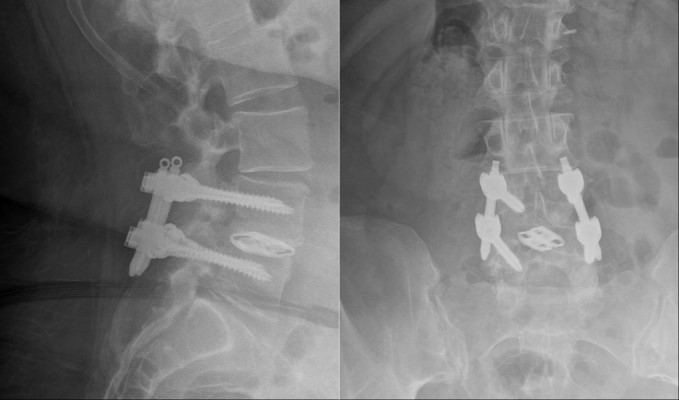

Postoperative x-rays showing lateral (side-view, left) and AP (front view, right) images of the lumbar spine with hardware in place. Note the correction of the spondylolisthesis.